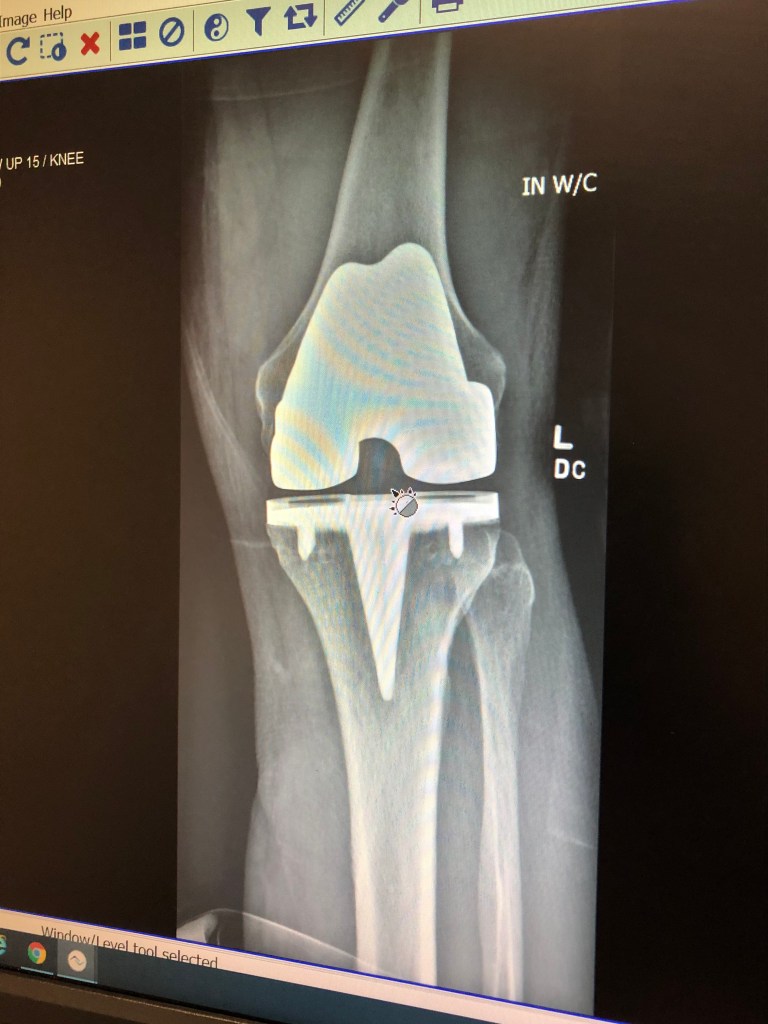

Our friendship continued to grow and discussions about life, our kids (we are proud dads!), the Bucs, and health entered the equation. I have learned a lot about and from Bob over the years and one thing is certainly true, this guy is a fighter. From competition, to life and in October (29) – a knee replacement. For someone who lives for duathlon like Bob does this was a major challenge to confront. Not only did he have the knee replacement, he needs another on the other leg so he has been and still is, in constant pain.

Bob’s new knee…

He has come a long way since October 29…wow!